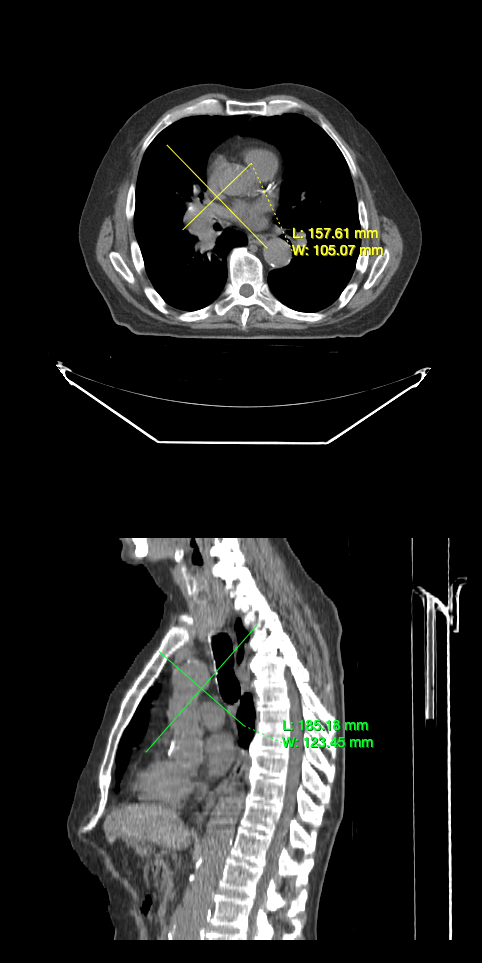

In this tutorial, you will learn how to use annotation tools to annotate.

You should be able to annotate images with the tools you added.